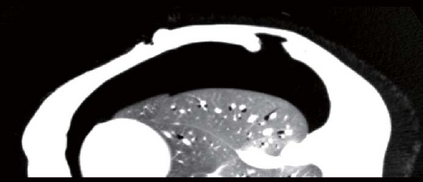

Recent advances in imaging techniques have enabled us to visualize lung tumors or nodules in early-stage cancer. However, the positions of nodules can change because of intraoperative lung deflation, and the modeling of pneumothorax-associated deformation remains a challenging issue for intraoperative tumor localization. In this study, we introduce spatial and geometric analysis methods for inflated/deflated lungs and discuss heterogeneity in pneumothorax-associated deformation. Contrast-enhanced CT images simulating intraoperative conditions were acquired from live Beagle dogs. Deformable mesh registration techniques were designed to map the surface and subsurface tissues of lung lobes. The developed framework addressed local mismatches of bronchial tree structures and achieved stable registration with a Hausdorff distance of less than 1 mm and a target registration error of less than 5 mm. Our results show that the strain of lung parenchyma was 35% higher than that of bronchi, and that subsurface deformation in the deflated lung is heterogeneous.